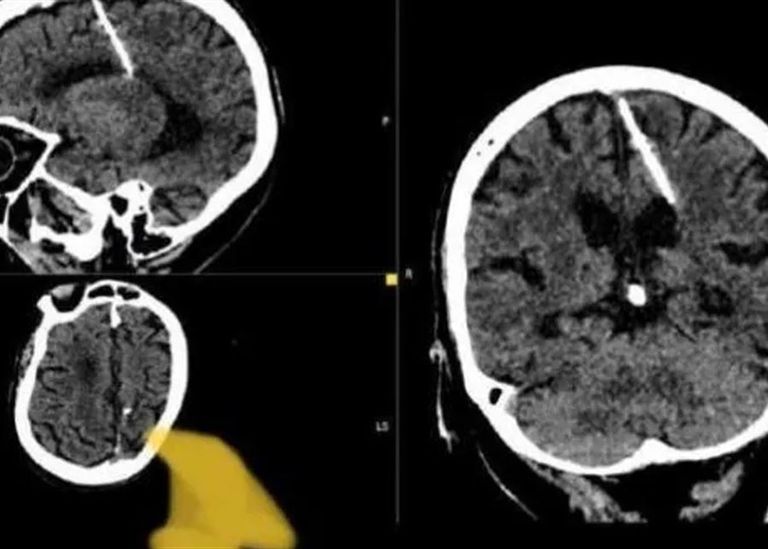

داخل دماغ امرأة مسنّة في أقصى الشرق الروسي، عثر أطباء على إبرة بطول 3 سنتيمترات موجودة منذ 80 عاماً.

وظهرت الإبرة أثناء عمل فحص بالتصوير المقطعي، ويعتقد الأطباء أن المرأة تعرضت لمحاولة قتل فاشلة نفذها والداها خلال طفولتها، وقالوا إنهما لم يحاولا إزالة الإبرة خشية أن يفاقم ذلك حالتها.

وقالت إدارة الصحة المحلية "لقد اخترقت الإبرة الفص الجداري الأيسر، لكن لم يكن لها التأثير المقصود، إذ نجت الفتاة".